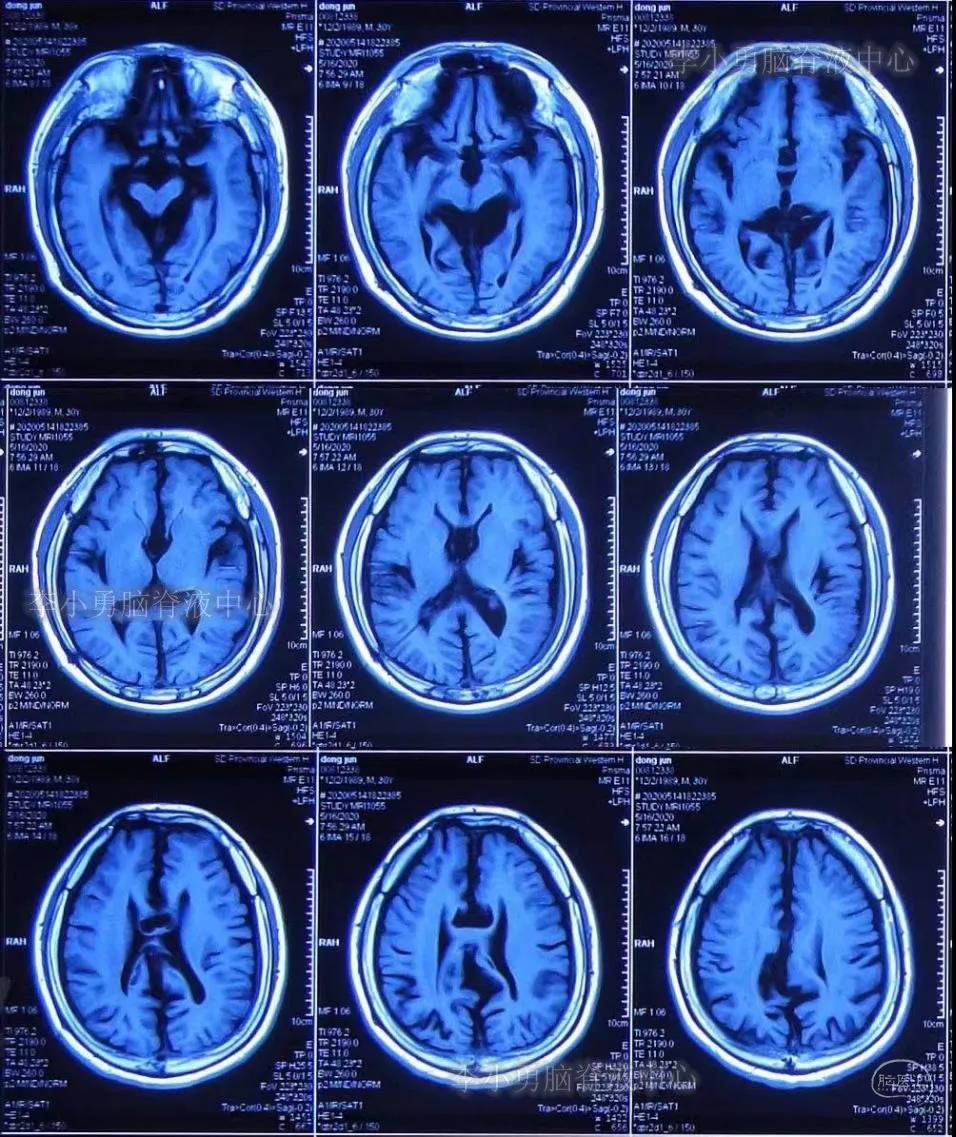

给予患者行腰穿检查提示“颅压增高”,但具体“原因不详”,给予甘露醇降颅压治疗,但症状无好转。于2020年5月16日给予行头部MR检查:仍未见异常(图-2)。

图-2:2020年5月16日头部MR